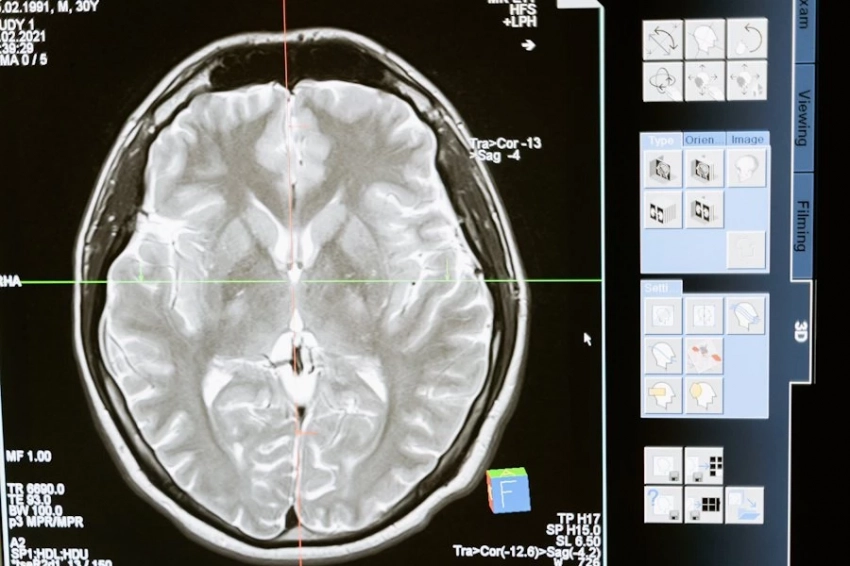

Новое исследование в Lund University (Швеция) показало, что привычка к чтению может значительно влиять на структуру мозга, особенно в областях, связанных с обработкой языка. У людей с навыками чтения обнаружены уникальные изменения в левом полушарии. Это, в частности, передняя височная доля, которая помогает связывать значения слов, и извилина Гешля, играющая ключевую роль в восприятии звуков языка.

Согласно изданию Neuroscience News, ученые отмечают, что чтение развивает толщину коры мозга в этих областях, что напрямую связано с лучшими навыками интерпретации и анализа информации. Интересно, что даже такие, на первый взгляд, «слуховые» зоны, как извилина Гешля, связаны с чтением, так как этот процесс требует фонологической обработки — способности сопоставлять буквы и звуки.